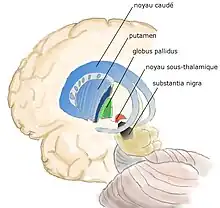

Au sens purement anatomique ils comprennent quatre noyaux pairs :

- le noyau caudé ;

- le noyau lenticulaire correspondant au putamen et au pallidum ;

- le noyau sous-thalamique ;

- la substance noire.